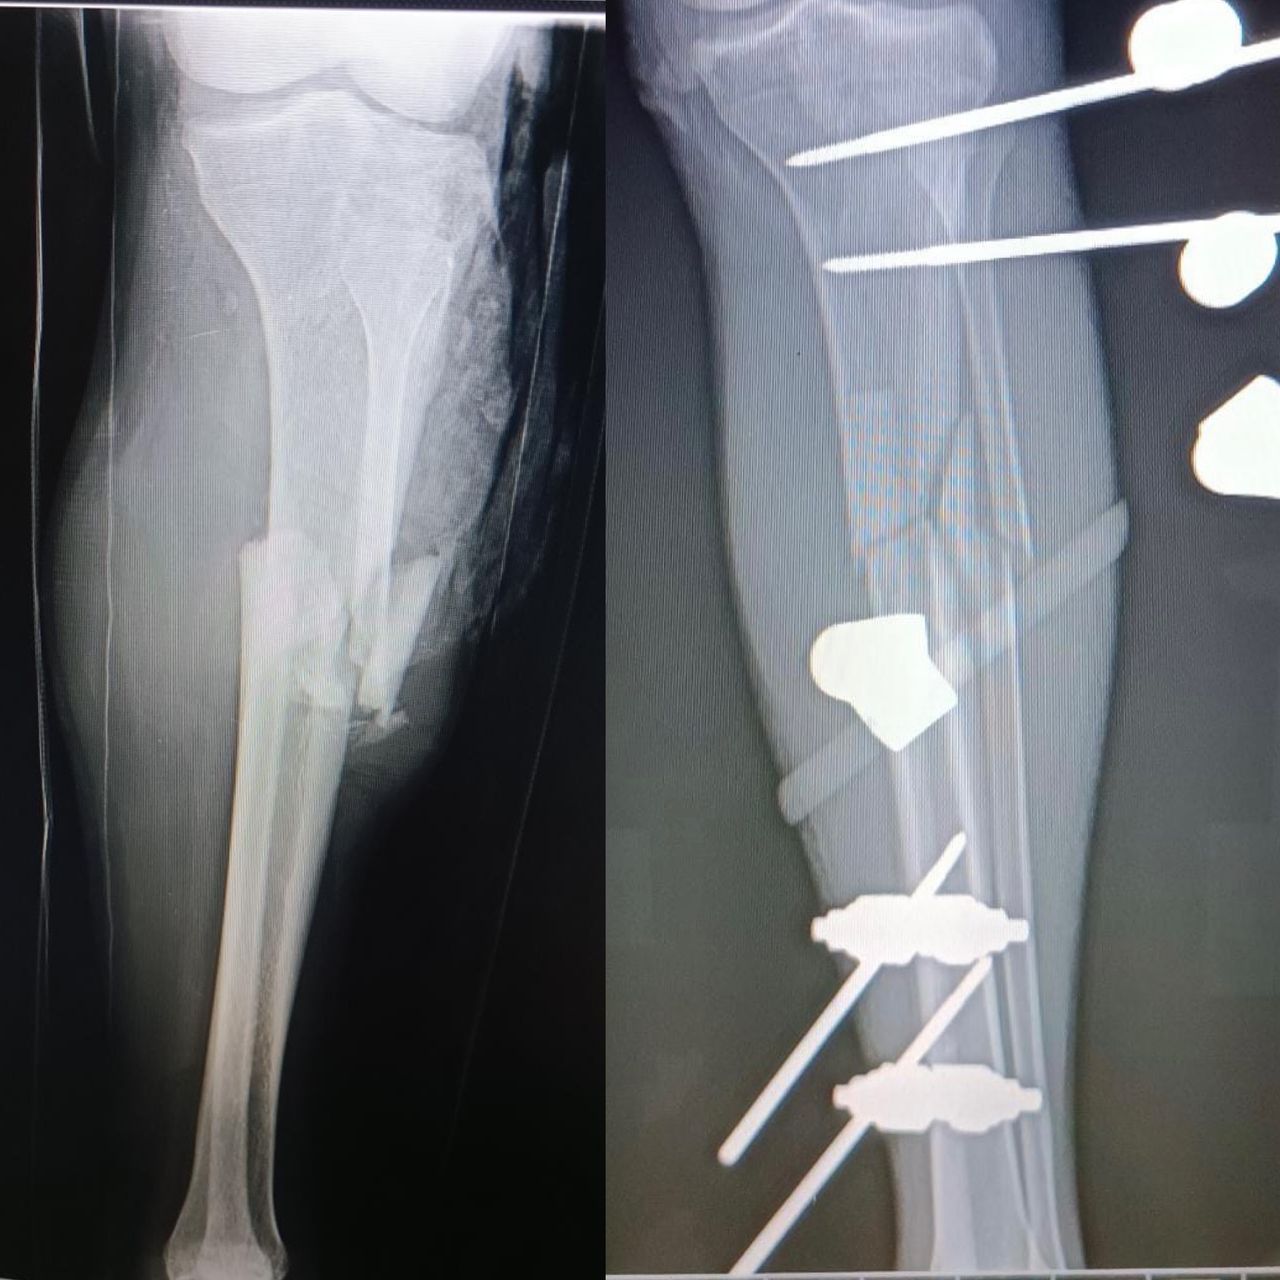

Fotos y videos

El doctor tiene mucha experiencia, muy buena atención y la ayuda de la toma de placas excelente.